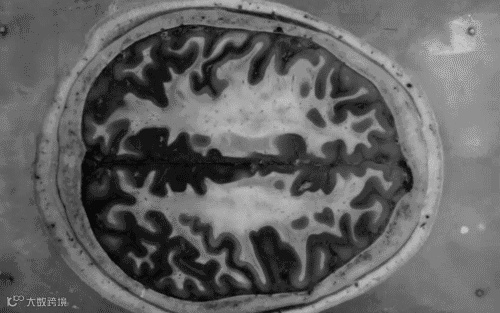

脑中风是一组以脑部缺血及出血性损伤症状为主要临床表现的疾病,又称脑卒中或脑血管意外,具有极高的病死率和致残率,主要分为出血性脑中风(脑出血或蛛网膜下腔出血)和缺血性脑中风(脑梗塞、脑血栓形成)两大类,以脑梗塞最为常见。脑中风发病急,病死率高,是世界上最重要的致死性疾病之一。中风的死亡率也有随年龄增长而上升的趋势。